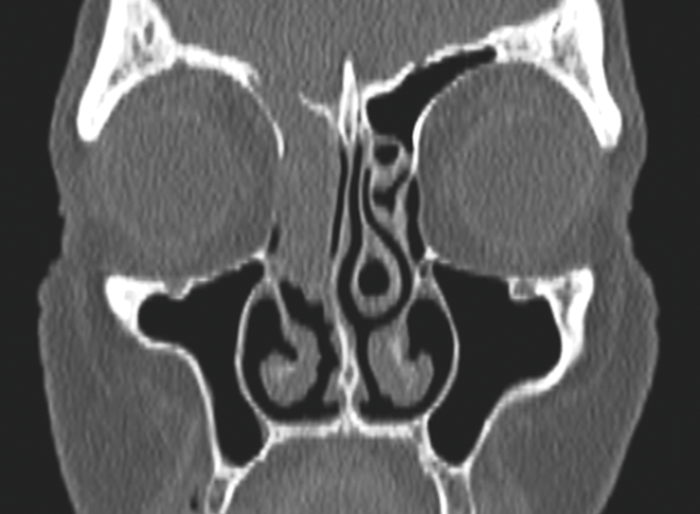

Functional Endoscopic Sinus Surgery (FESS) - Part 2

In the first of this two-part series, Martyn Barnes and colleagues discussed indications for functional endoscopic sinus surgery (FESS), the surgical objectives and techniques, patient expectations and the risks of surgery [1]. In this second and final part, the authors...